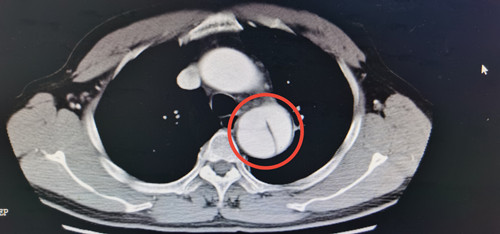

邓先生到湖南省人民医院马王堆院区呼吸内科门诊就诊时,接诊的医生通过仔细询问病情,发现问题,遂安排其进行了胸部CT检查,发现主动脉夹层,病情凶险,立即转入介入血管外科三病区救治。

邓先生入院后,测量血压180/90mmHg,经CTA(CT血管造影)等检查,明确诊断为主动脉夹层B型,主动脉被撕开成两半,随时有破裂大出血死亡风险,需手术治疗。经完善手术准备,邓先生接受了全麻下主动脉夹层腔内隔绝术,术中用一枚支架修复主动脉的破口,拆除了随时可能爆炸的“炸弹”。术后邓先生经过康复,已于今日出院。邓先生的家人表示:“以前没听说过血管夹层这种病,没想到普通的一个咳嗽还可能是要命的病,多亏当时医生提醒,才得以及时救治。”